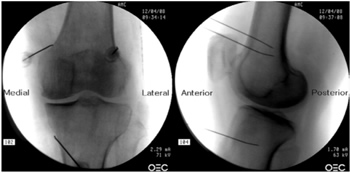

Radiofrecuencia de los nervios geniculados guiados por fluoroscopia

Para realizar una RFTNG guiados por fluoroscopia necesitamos una visión anteroposterior (AP) y lateral de la rodilla (Figura 2). Primero ubicamos al paciente en posición supina con una almohada debajo de la fosa poplítea (para que esté más cómodo) (16). Después de realizar asepsia y antisepsia de la rodilla, procedemos a ubicar los NG (Tabla II). El NGSL se encuentra avanzando la aguja de RFT hacia la confluencia de la diáfisis femoral lateral con el cóndilo femoral lateral en una visión AP y en un punto medio del fémur en una visión lateral. El NGSM se localiza avanzando la aguja hacia la confluencia de la diáfisis femoral medial con el cóndilo femoral medial en una visión AP y en un punto medio del fémur en una visión lateral. Por último, el NGIM se localiza avanzando la aguja hacia la confluencia de la diáfisis tibial medial con el epicóndilo tibial en una visión AP y en un punto medio de la tibia en una visión lateral (16,17).

Fig. 2. Proyección AP y lateral donde se observan las dianas terapéuticas usando fluoroscopia. Imagen tomada del artículo de Choi y cols. (9). Reproducido con la autorización de Jin Woo Shin.

Tabla II. Localización de los nervios geniculados guiados por fluoroscopia

Es muy importante tener una buena visión AP y lateral. En la proyección AP, la articulación tibiofemoral debe tener una anchura similar a ambos lados de la rodilla con el interespacio abierto (9). En la proyección lateral, debe existir una correcta superposición de ambos cóndilos femorales para realizar un bloqueo satisfactorio de los NGSM y NGSL (18).

La mayoría de autores toman las referencias descritas previamente para localizar estos nervios por fluoroscopia, excepto Fonkoué y cols. (18), quienes encuentran que las dianas terapéuticas del NGSM y NGSL (en una visión lateral) se encuentran en la unión del borde superior de sus respectivos cóndilos femorales con la corteza posterior de la diáfisis del fémur, y no en la mitad del espesor del fémur, como se describe clásicamente (9,10,13).

Dado que el éxito de la RFT de los nervios geniculados depende de la correcta ubicación de la punta de la aguja de RF (lo más cerca que se pueda al nervio), Know y cols. (17) demostraron con imágenes de resonancia magnética que los puntos que se usan clásicamente en fluoroscopia para la ablación de los tres nervios geniculados (NGSM, NGSL y NGIM) son correctos. Observaron que los NG pasan por la intersección formada por la línea diafisiaria y metafisiaria del fémur distal o de la tibia proximal (NGSL 92 %, NGSM 88 % y NGIM 100 %).

Después de ubicar la aguja de RFT (22G de 100 mm con punta activa de 10 mm) en los puntos deseados, procedemos a confirmar la posición del nervio utilizando un estímulo sensitivo a 50 Hz; el umbral de estimulación sensorial con el cual el paciente percibe una parestesia o dolor debe ser menor a 0,6 V. Luego confirmamos la ausencia de fasciculaciones en la extremidad inferior usando una estimulación motora a 2 Hz con 2,0 V. Finalmente se administra 2 ml de lidocaína al 2 % o mepivacaína al 2 % en cada nervio, y se inicia la RFT a 80 °C durante 90 segundos (9,14).